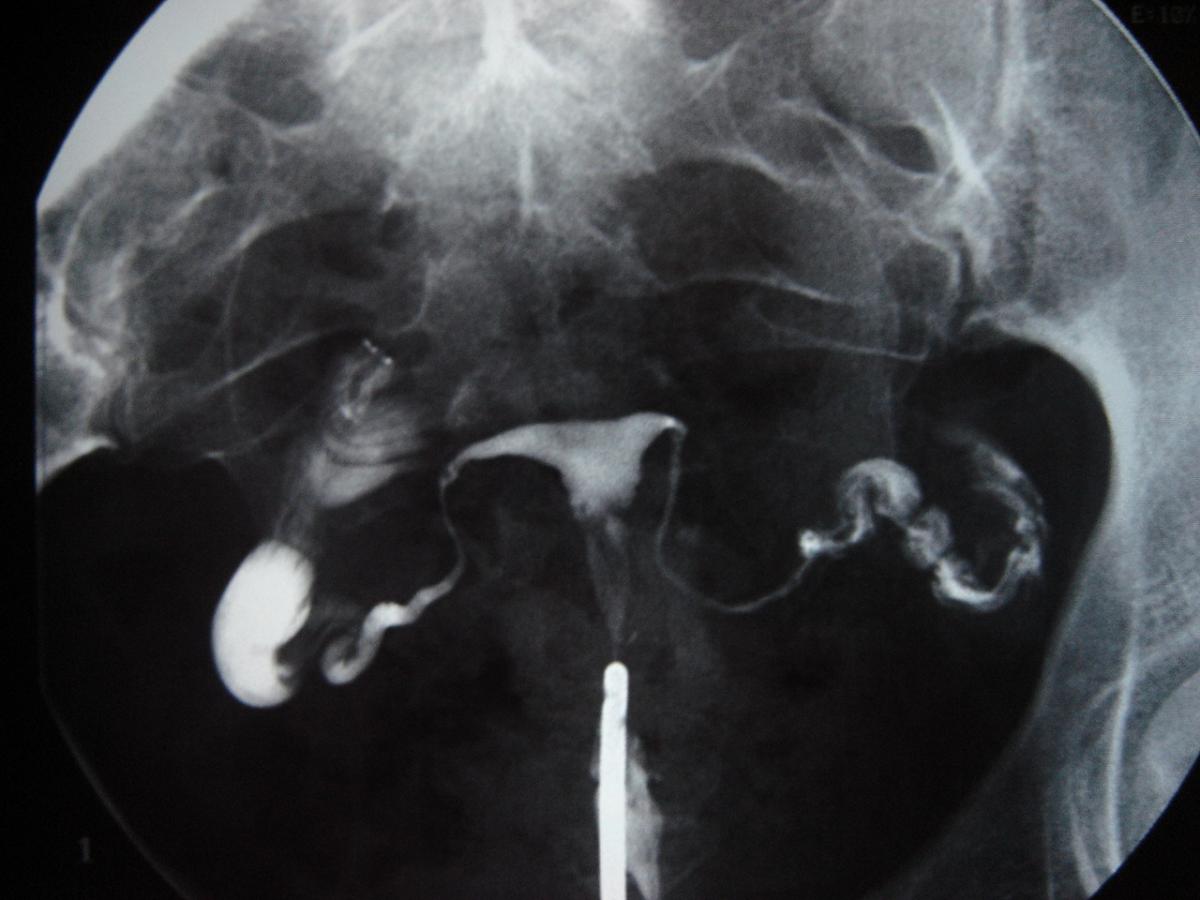

Qué es la histerosalpingografía

La histerosalpingografía es el estudio radiológico del útero y las trompas de Falopio que estudia su funcionalidad. Es una técnica médica que debe ser realizada por un ginecólogo y un radiólogo conjuntamente. En unComo.com queremos explicarte con más detalle qué es la histerosalpingografía para que no te quede ninguna duda.

Para llevar a cabo el procedimiento la mujer debe adoptar la posición de litotomía (posición de exploración ginecológica o parto) en una mesa de exploración con estribos. El ginecólogo introducirá un espéculo en vagina con un tentáculo fijo a este para fijar la cavidad uterina (el cuello cervical). Tras posicionar el espéculo el ginecólogo administrará el contraste con la ayuda de una cánula en la cavidad uterina y en las trompas de Falopio. Cuando ambas están completas, con el contraste se realizan las radiografías.